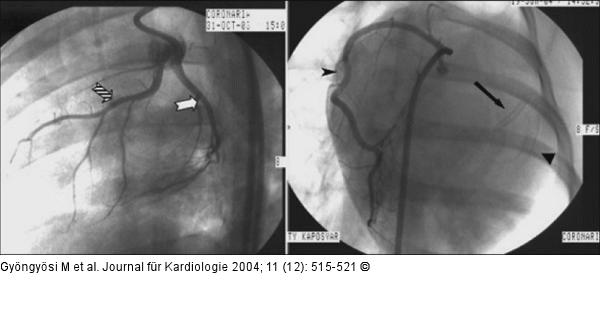

Abbildung 1: Arteria coronaria - Hausschwein Linke Koronararterien (links) (LAD, LCx) und rechte Koronararterie (rechts) beim Hausschwein; AP-Aufnahme → Stent (2,75 mm/18 mm) in der LAD, Stent (4,0 mm/18 mm) in der LCx |

Linke Koronararterien (links) (LAD, LCx) und rechte Koronararterie (rechts) beim Hausschwein; AP-Aufnahme → Stent (2,75 mm/18 mm) in der LAD, Stent (4,0 mm/18 mm) in der LCx |